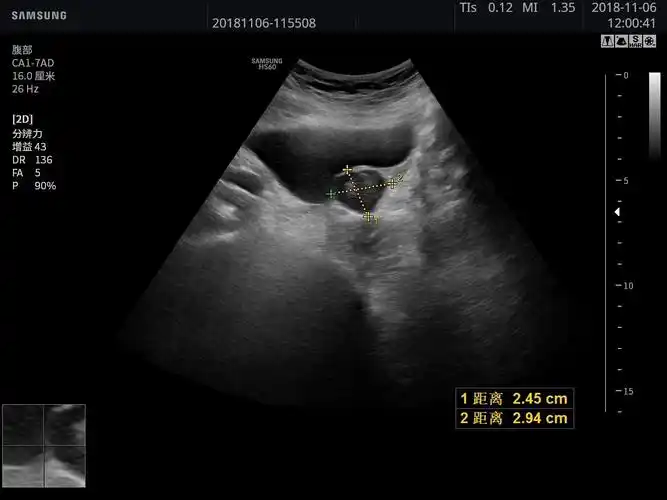

超声入门贴41膀胱癌

彩超提示膀胱内实质性占位病变,考虑膀胱肿瘤膀胱镜检示右侧壁菜花状

超声入门贴41-----膀胱癌

膀胱内实性占位考虑为膀胱癌

膀胱占位